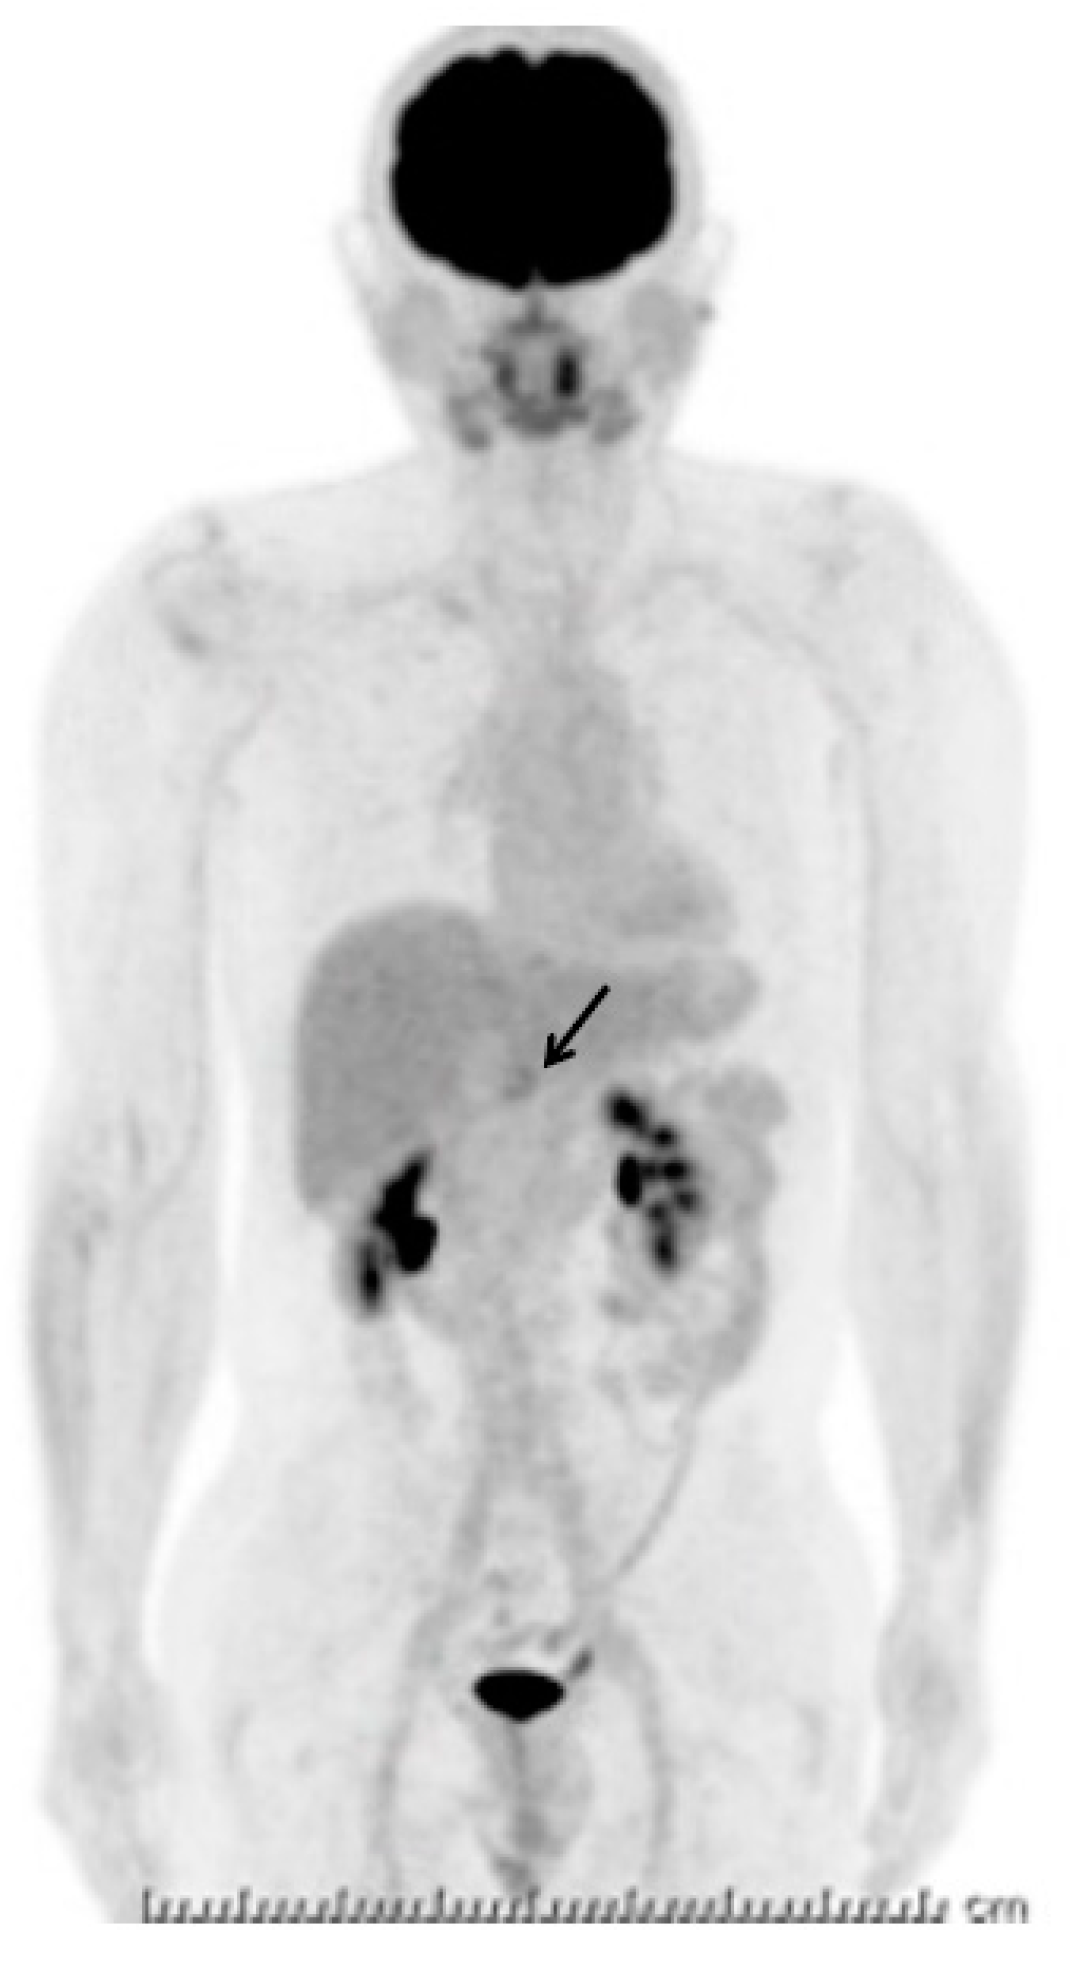

A Multinodular Mass of Abdominal Splenosis: Case Report of Uncommon Images of a Rare Disease

2. Case Presentation